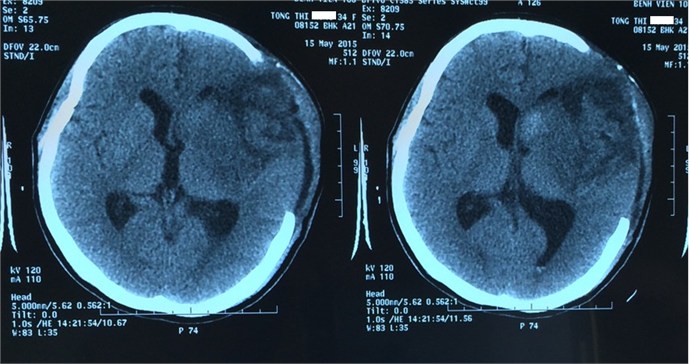

Tai biến mạch máu não là một rối loạn khu trú của não bộ nguy hiểm và phổ biến nhất hiện nay đặc trưng bởi hiện tượng máu lên não bị gián đoạn đột ngột với hai dạng chính là nhồi máu não (tắc mạch máu) và xuất huyết não (vỡ mạch máu), có tiến triển nhanh trên lâm sàng vì bệnh thường do một mạch máu não bị vỡ hoặc tắc đột ngột.

- Nhồi máu não (chiếm 80%): Nhồi máu não xảy ra khi một vùng não không được cấp máu. Tình trạng bít tắc này kéo dài gây cản trở máu lưu thông đến não, khiến các tế bào não bị thiếu hụt oxy quá mức và chết.

- Xuất huyết não (chiếm 20%): Xuất huyết não xảy ra do một mạch máu não bị vỡ, khiến máu thấm vào mô não và từ đó gây tổn thương cho các tế bào não.